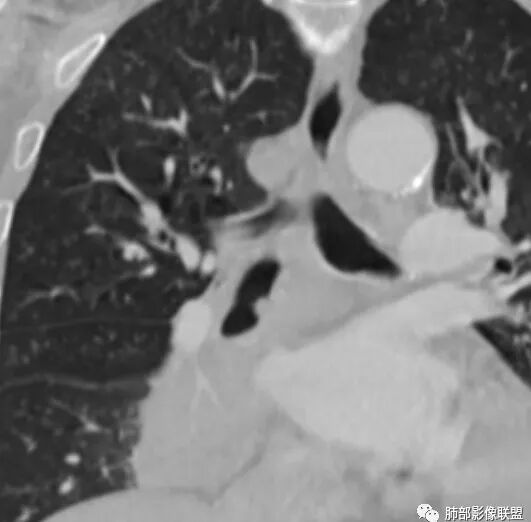

第1个问题:是否是近端支气管堵塞?腔内肿瘤导致远端阻塞性改变?还是外围病灶围绕支气管,引起堵塞?

第2个问题:病灶是否就是内基底段?

第3个问题:支气管堵塞?还是堵塞后还有通畅支气管?

这是支气管,注意看视频支气管连续性的变化。如果上面的支气管完全堵塞,下面的支气管如何解释?

大家考虑这个是支气管腔内占位?引起远端阻塞?还是外围为主病灶侵犯支气管?

南边:个人倾向于外周为主病灶,腔内改变是继发的。原因:病灶围绕支气管,腔内远端无明显阻塞性不张。

边缘偏平直,内部血管走形自然,一般提示包绕为主。

琦遇:好病例!支气管爬行;右肺中叶有树芽征;右侧分支支气管壁弥漫性增厚了。右肺下叶内基底段支气管通而不畅。

(2)支气管和血管:右肺支气管分支管壁弥漫性增厚,中间段支气管散在结节样凸起,右肺下叶内基底段支气管闭塞,但远端可疑复出。余病灶围绕支气管腔内远端无明显阻塞性不张。内部血管走形自然,提示包绕为主。